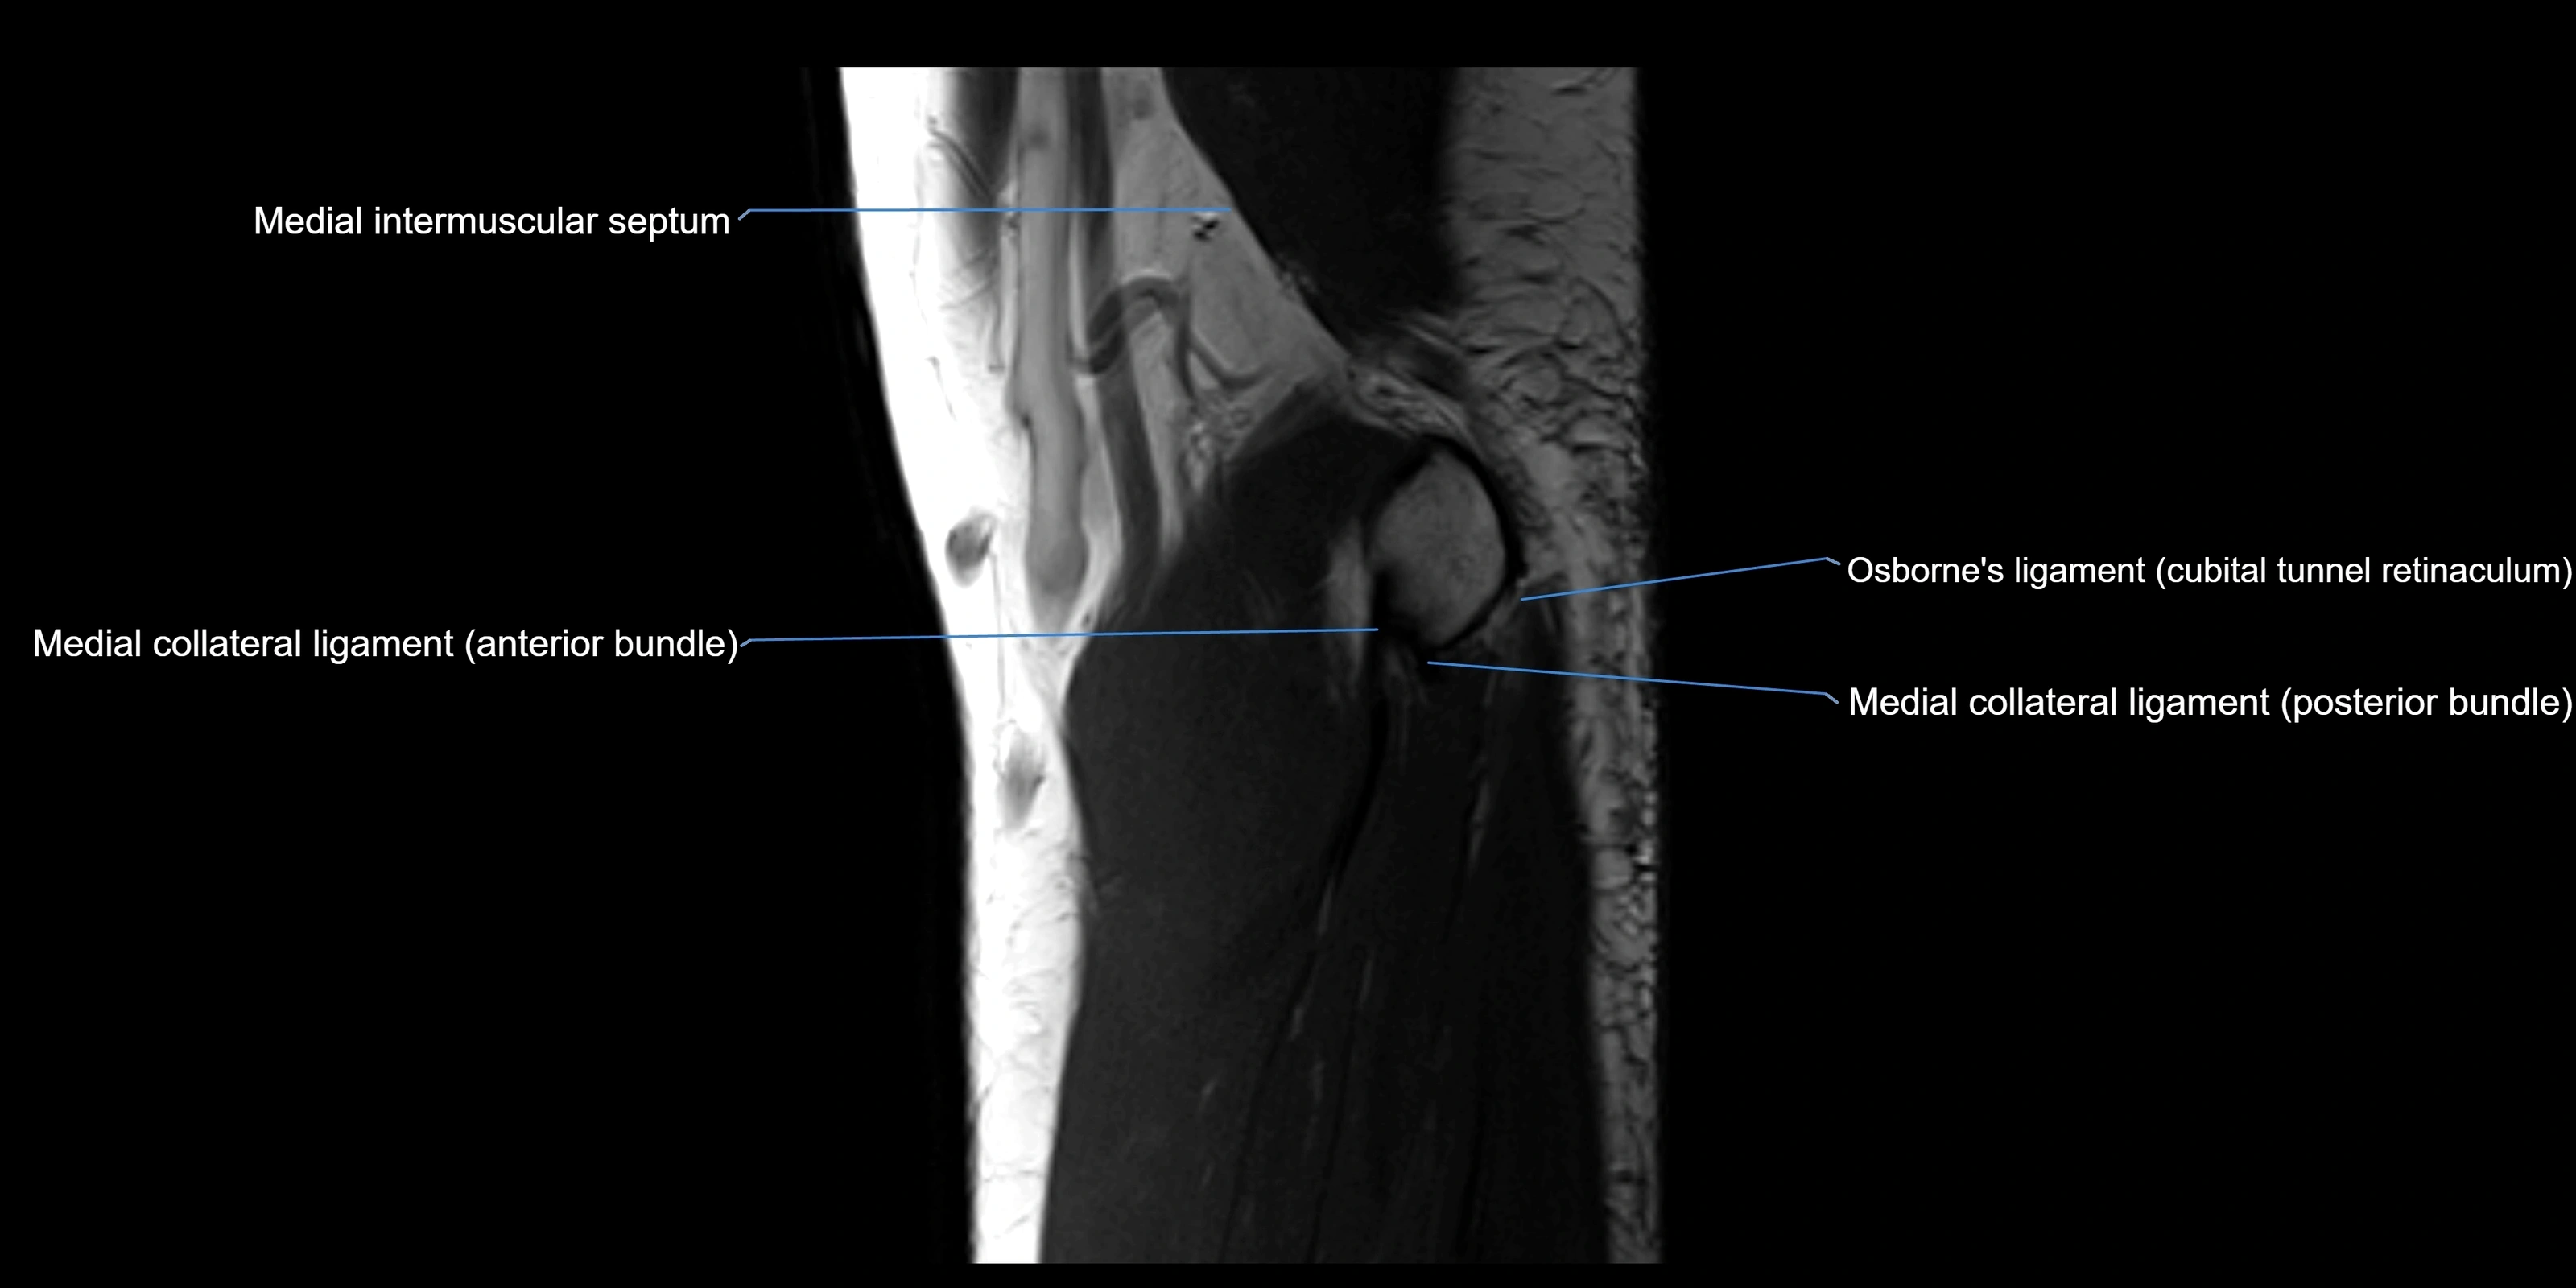

MRI Appearance

T1-weighted images:

• Ligament: low signal intensity (dark), appearing as a continuous band around the radial head.

• Adjacent fat and marrow: bright, creating contrast with the ligament.

• Thickening or disruption indicates injury or fibrosis.

• Joint capsule and synovium seen as thin low-signal lines contiguous with ligament margins.

T2-weighted images:

• Ligament: low signal (dark) with clear delineation from joint fluid.

• Fluid or edema: bright hyperintense, separating or surrounding the ligament in partial tears.

• Complete tear: discontinuity or non-visualization of ligament fibers, often with joint effusion.

MRI images

image